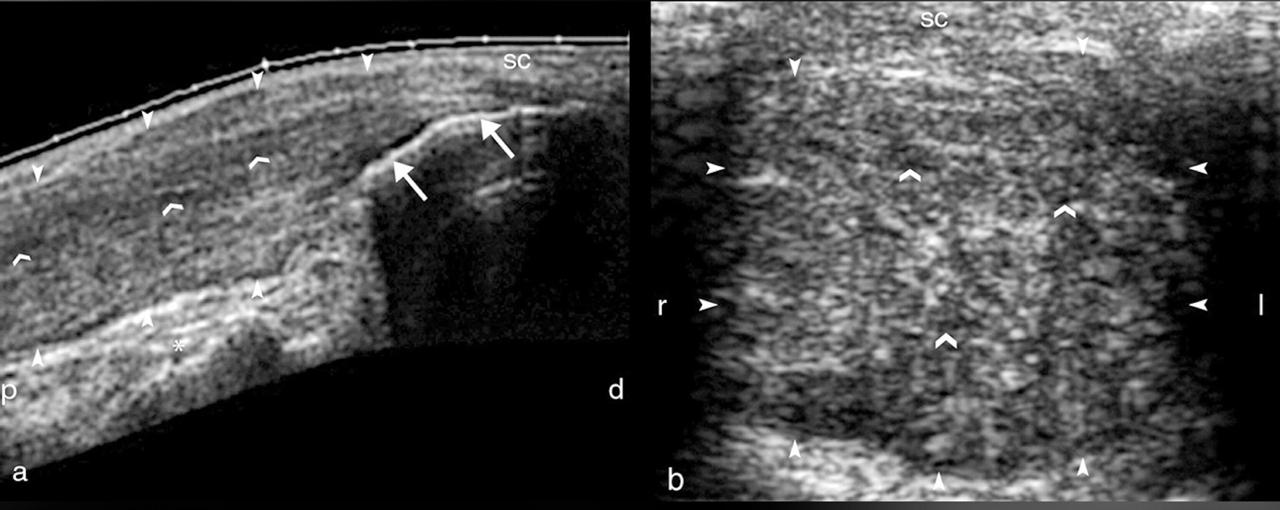

DEVELOPMENTAL DYSPLASIA OF THE HIP (DDH)

Developmental dysplasia of the hip (DDH) is one of the most common musculoskeletal problems in newborns. It results from an abnormal relationship of the femoral head to the acetabulum. The reported incidence of DDH varies between 1.5 and 20 per 1000 births, with a clear female predominance (M:F ratio ~1:8). DDH usually occurs from ligamentous laxity and abnormal position in utero. For some reason, the left hip is said to be more frequently affected. One-third of cases are affected bilaterally.

Ultrasound is the modality of choice for imaging assessment of DDH in the infant (<6 months) prior to ossification of the proximal femoral epiphysis. A lineair, high frequency probe is used and the focus is set at the acetabular edge. Once there is a significant ossification then x-ray examination is required.

The Graf classification of hip dysplasia is mainly based on the morphology of the iliac bone, where we look at the shape of the acetabulum, the bony and cartilaginous acetabular rim, labrum and position of the femoral head, and also look at the coverage of the femoral head by the cartilage of the acetabulum and the labrum.

The alpha-angle, which is a measurement of the bony roof of the acetabulum, mainly determines the hip type. The normal value is greater than or equal to 60º. Note that up to the age of 3 months (13 weeks) an alpha angle below 60 degrees is acceptable.

The beta angle is formed by the vertical cortex of the ilium and the triangular labral fibrocartilage. The normal value is less than 77º but is only useful in assessing immature hips when combined with the alpha angle, to differentiate between type Ia and Ib (both normal hips) and between type IIc and type D.

Bony coverage represents the percentage of the femoral epiphysis covered by the acetabular roof. A value of >50% is considered normal.

Treatment varies from Pavlik bracing to surgical reduction and osteotomies depending on the age of the patient and the degree of dysplasia.